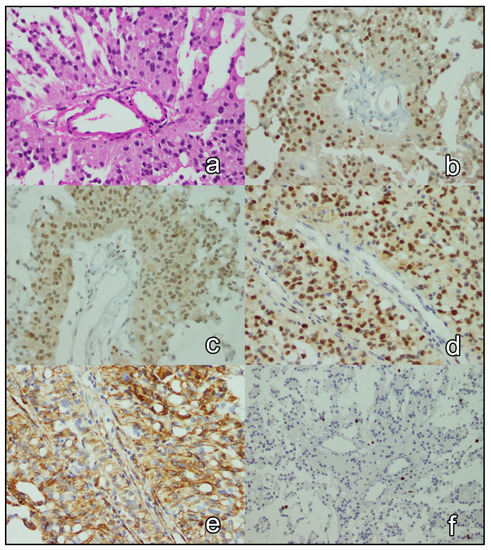

Immunohistochemical Expression of p27Kip1, p57Kip2, Cyclin D1, Nestin, and Ki-67 in Ependymoma

3.3. Immunohistochemical Analysis